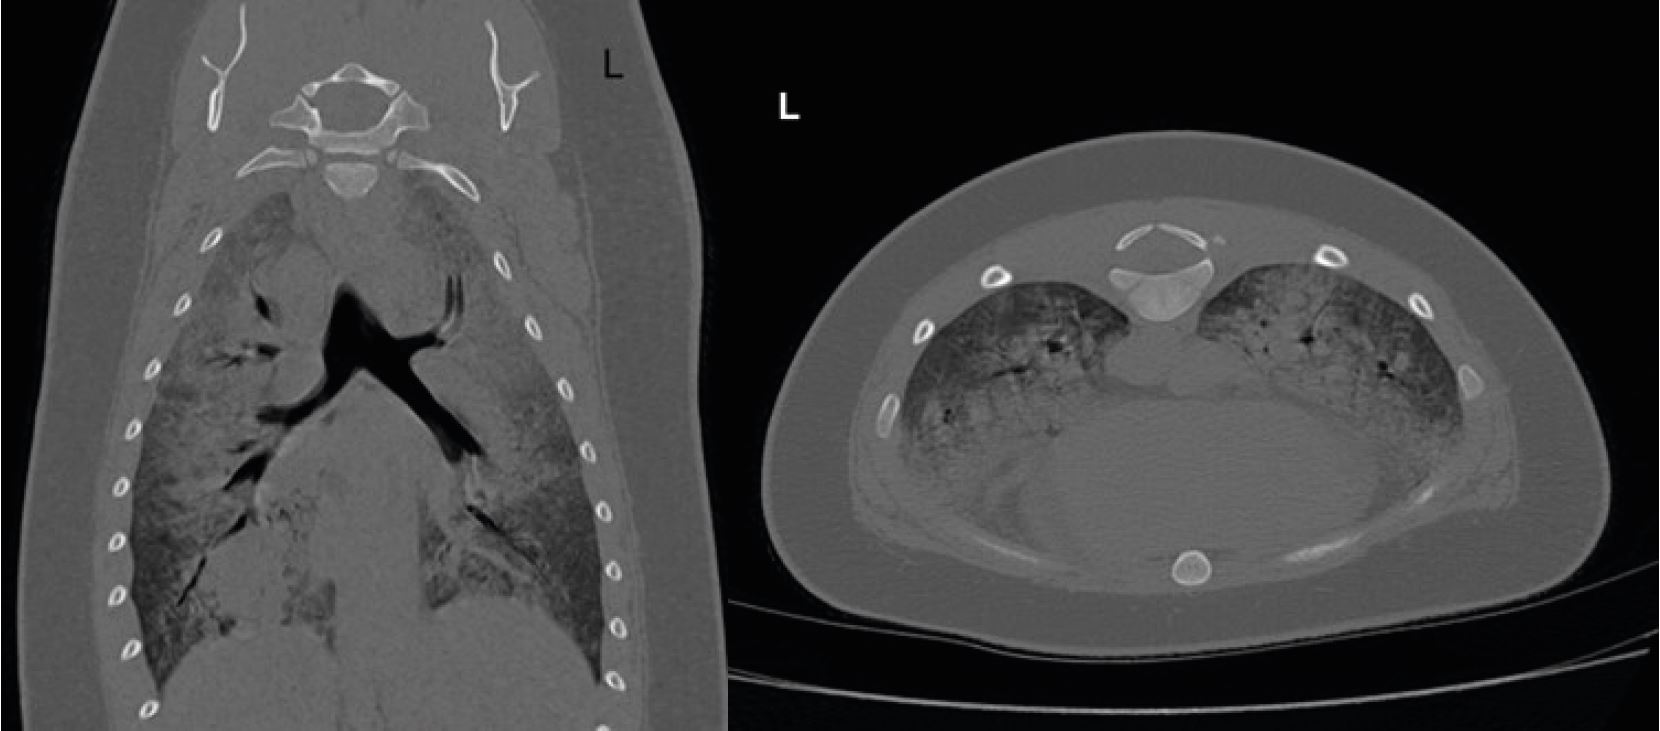

Елвіс продемонстрував ненормальну ходу та, ймовірно, біль у тазі. При таких проблемах, як переломи хребта. Для виключення вивиху або перелому кісток таза виконано КТ (мал. 3). КТ не виявила ознак переломів і вивихів.

Малюнок 2: Жодних аномалій не спостерігалося на обох реконструкціях кісткового фільтра

Малюнок 3: Не було виявлено аномалій у будь-якому напрямку у кістковій реконструкції.